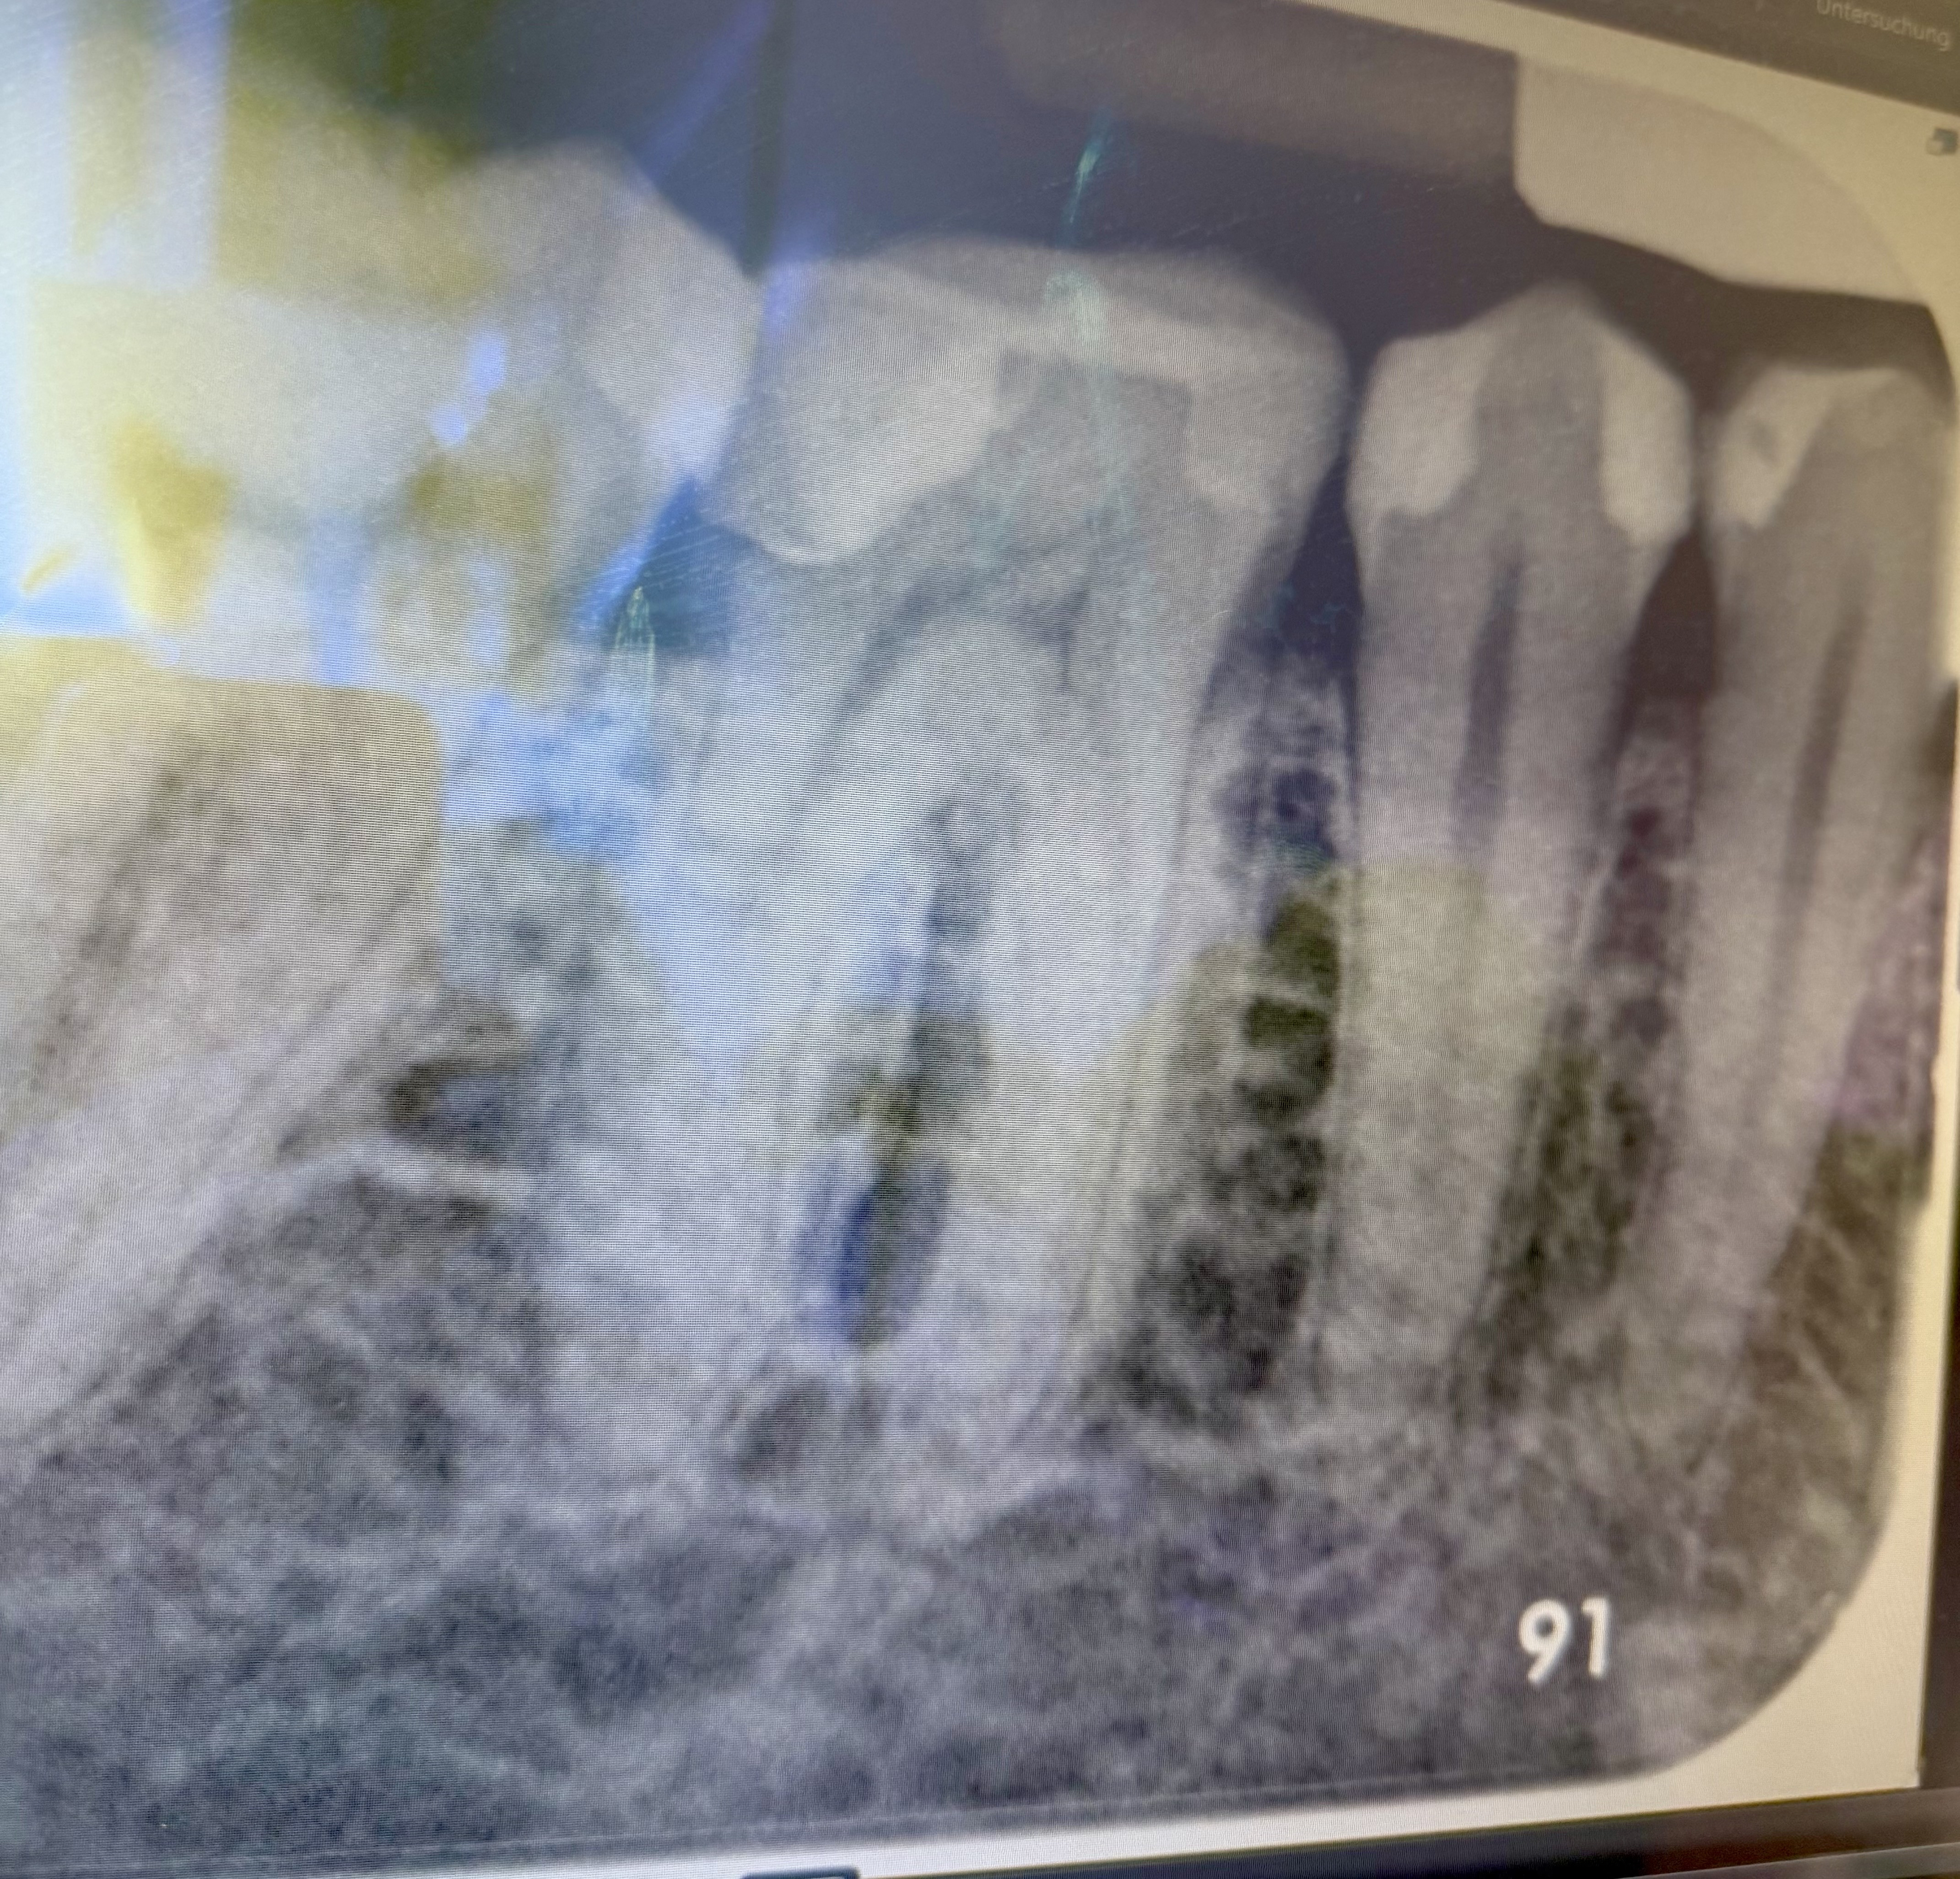

Es wurde ein Röntgenbild gemacht und ich habe dazu zwei verschiedene Zahnärzte gefragt und die sind völlig unterschiedlicher Meinung:

Hier ist das Bild des Zahnes: